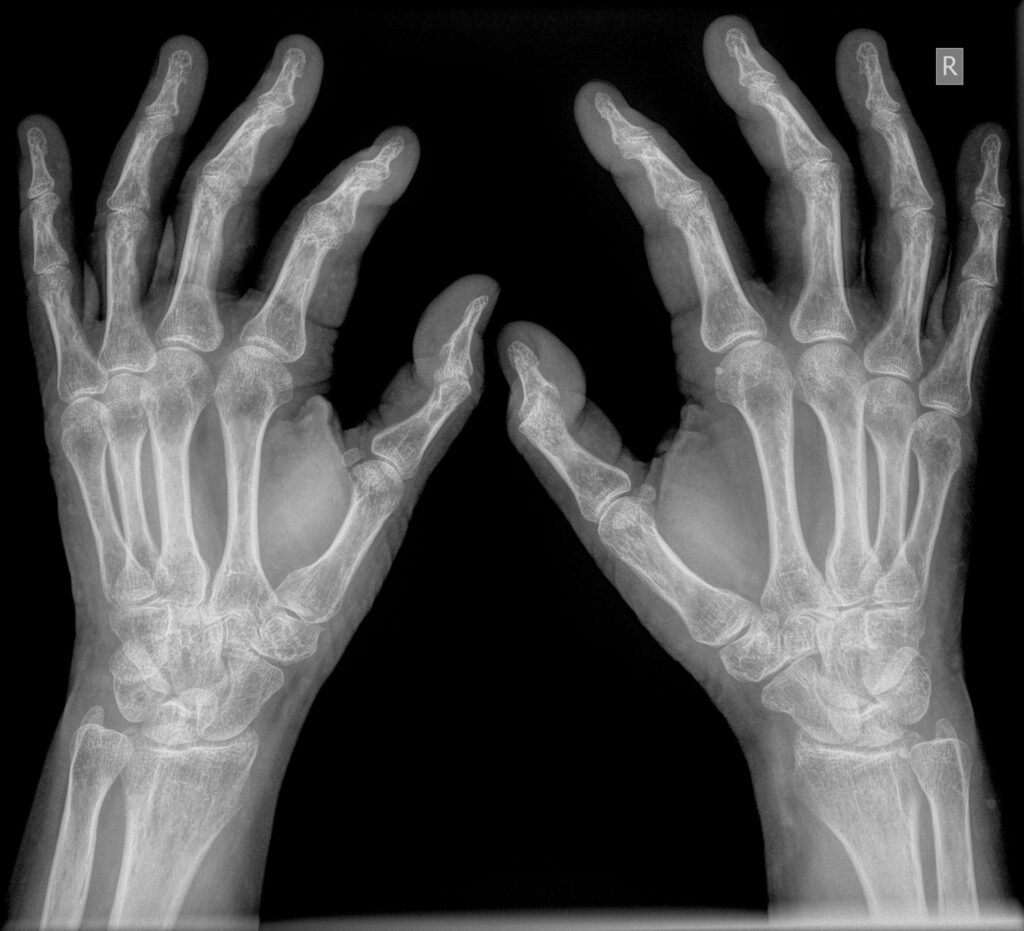

Hvor traditionel billedbehandling justerer kontrasten globalt, arbejder MUSICA3 på et mikroniveau. Hvert billede opdeles i lag – hvert lag behandles separat – og resultatet er, at du ser detaljer, der ellers ville forsvinde i overgangszonerne mellem lyst og mørkt væv.

Det gælder særligt i de klinisk vanskelige områder.

- Balanceret fremstilling af blødt væv og overlappende knogler

- Tydelig knogleadskillelse ved ortopædiske implantater

- Optimeret visning af trabekulære mønstre i knogle